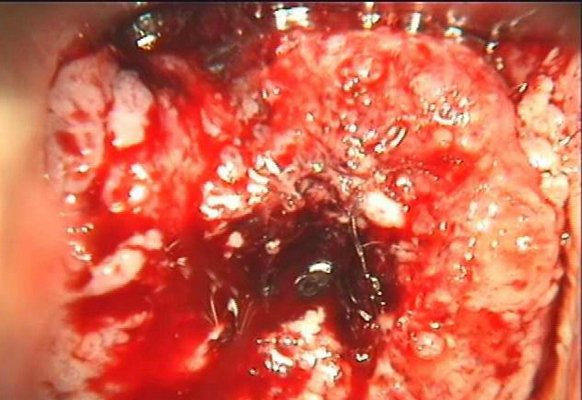

子宮頸糜爛圖片

宮頸糜爛 (57)